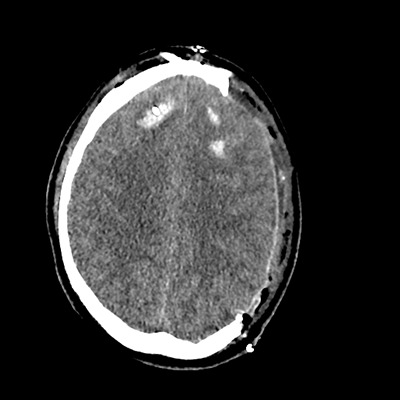

On day 5 of admission, he begins having intracranial hypertension again, spiking up to 40mmHg. You bolus with propofol and fentanyl, to no avail. You then push 30mL of 23.4% NaCl, which provides some brief improvement, allowing you to quickly get a non-contrast head CT. Unfortunately, he's now back up to 36mmHg. You review his labs, and note the following: Na 150, K 3.8, Cl 119, HCO3 18, BUN 21, Cr 0.85, glucose 136, sOsm 320.

NCHCT

NCHCT 4/20 4/20